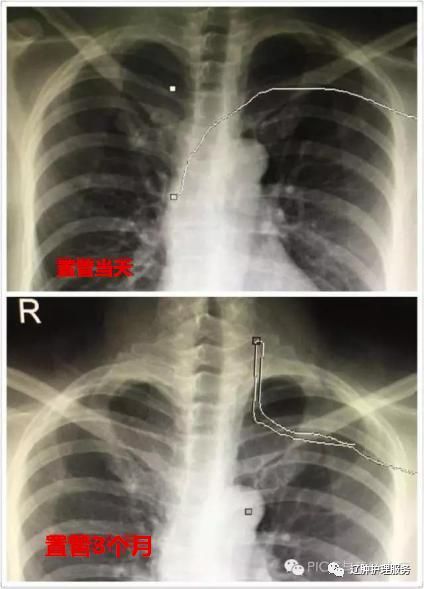

2.导管异位、打结:由于各种原因引起上腔静脉内压力突然增加或患者个体血管的解剖变异 , 都可能导致异位以及导管打结 。